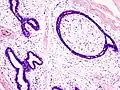

Fibroadenoma histology (H&E). The image demonstrates intracanalicular morphology (bottom left) and pericanalicular morphology (top right) -